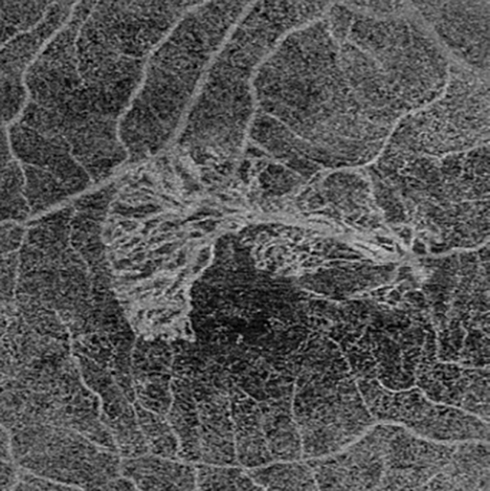

Many patients during the first stage of Covid-19 missed essential treatments and have experienced a progression of their eye condition. We encourage patients to keep their appointments.